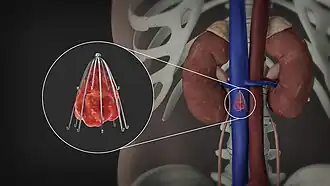

An inferior vena cava filter is a medical device made of metal that is implanted by vascular surgeons or interventional radiologists into the inferior vena cava to prevent a life-threatening pulmonary embolism (PE) or venous thromboembolism (VTE).[2][3]

The filter is designed to trap a blood clot and prevent its travel to the lung where it would form a pulmonary embolism.[4][3] Their effectiveness and safety profile is well established, and they may be used when anticoagulant treatment is not sufficient.[5]

Placement

IVC filters are placed endovascularly, meaning that they are inserted via the blood vessels. Historically, IVC filters were placed surgically, but with modern filters that can be compressed into much thinner catheters, access to the venous system can be obtained via the femoral vein (the large vein in the groin), the internal jugular vein (the large vein in the neck) or the arm veins with one design. Choice of route depends mainly on the number and location of any blood clot within the venous system. To place the filter, a catheter is guided into the IVC using fluoroscopic guidance, then the filter is pushed through the catheter and deployed into the desired location, usually just below the junction of the IVC and the lowest renal vein.[44]